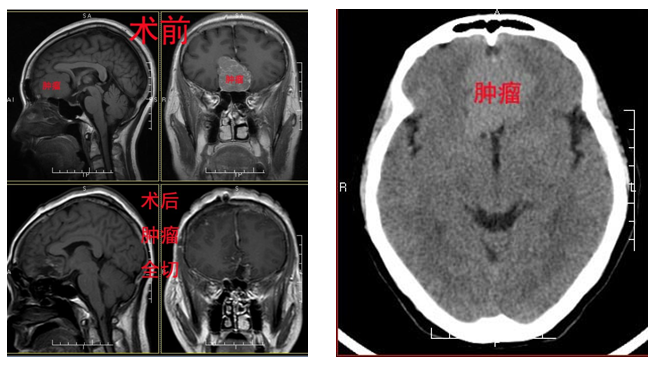

患者徐某某,59岁,女性,聊到病情时病人有少许的激动,头痛从3年前就开始了,以为是退休引起的不适,就没有太在意,休息不能缓解时,吃止痛药就缓解,一直没有想过要去医院检查,入院前一周头痛处理都无法缓解,又听别人聊天说,谁谁谁也是头痛去医院检查就是肿瘤晚期。徐小姐听到吓到背脊出冷汗,就赶紧去医院做检查,果不其然,收到结果那一刻,徐小姐瘫坐在椅子上。2015-12-19收入我院;体查未见明显阳性体征;辅助检查:外院头颅MR检查示:前颅窝底巨大占位,考虑脑膜瘤。入院后予以手术治疗,术后病理回报提示:皮细胞型脑膜瘤WHO分级I级。

嗅沟脑膜瘤起自筛板部位的硬脑膜,是颅前窝肿瘤中最常见的一种。其临床症状主要有:嗅觉障碍,颅内压增高引起头痛,视力障碍,癫痫和精神、行为异常等。但由于额叶相对于哑区,早期症状不太明显而被忽略,致使肿瘤发现时体积已经较大,由于肿瘤体积大,因此手术的难度随之增加。显微器械的应用减少了手术的死亡率,提高了手术的全切率,为巨大嗅沟脑膜瘤的切除提供了必要的保证。手术者的临床经验也是非常重要的,它要求术者对肿瘤周围的结构十分了解及变异的变化。